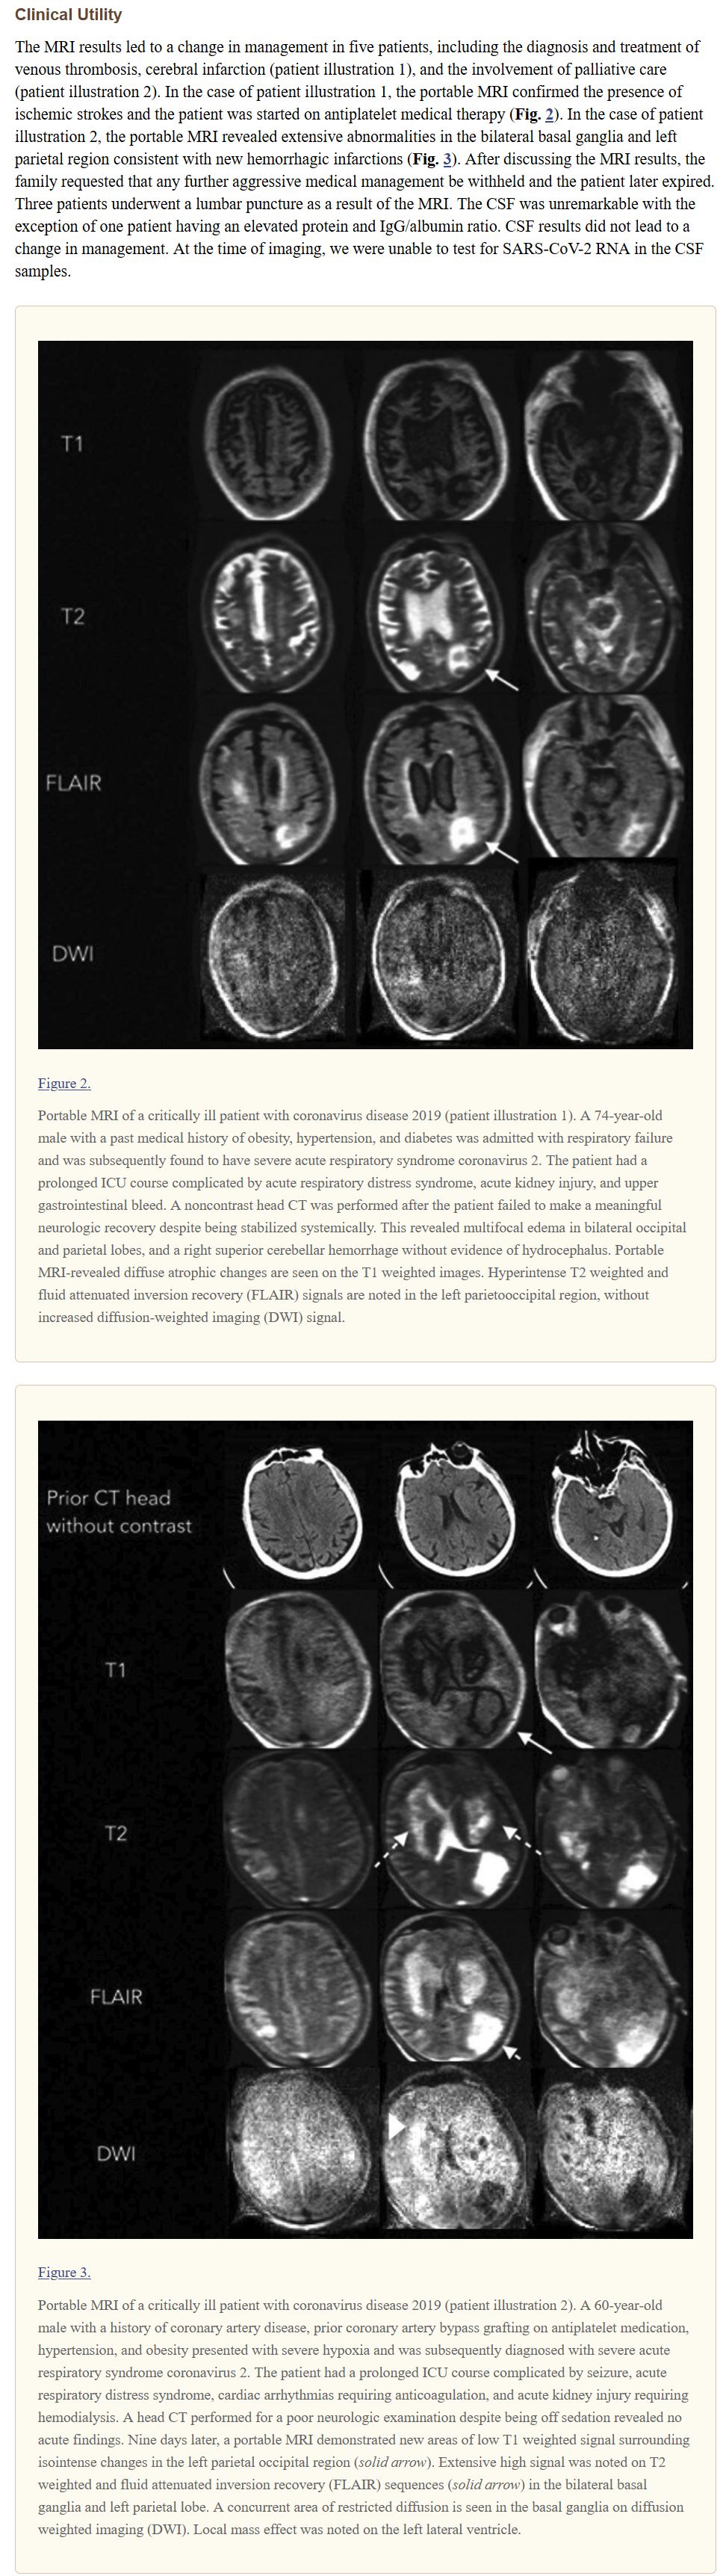

FDA 승인도 받았습니다. 기존 MRI보다 해상도가 낮아 완전 대체는 안 되지만, 소형이고, 일반 엘리베이터로도 이동이 가능한 크기고, 태블릿으로 조작 가능하고, 자석이 0.064T 정도라 별도의 보호 조치가 필요하지 않고, 일반 전기 아웃렛;콘센트 사용 가능하다고 합니다. 코로나19 시대에는 격리 병실에서도 사용 가능한 것이 또 장점이라고.